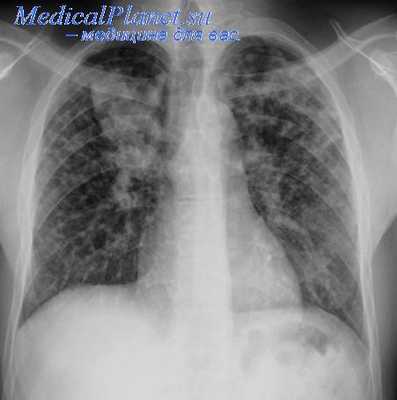

Подготовка к операции Якобеуса заключается прежде всего в постепенном доведении давления в плевральной полости до нуля, чтобы вскрытие ее не повлекло значительного изменения дыхания. Для этого увеличивают количество вводимого воздуха и частоту поддуваний, в течение 10—15 дней достигая выравнивания давления.

Если при этом больной испытывает тягостные ощущения или одышку, то операция откладывается до момента привыкания к большому коллапсу или вообще отменяется. Нужно, чтобы толщина слоя воздуха между грудной стенкой и легким была не менее 4 см. Если в плевральной полости имеется выпот, то стараются уменьшить его путем осторожных отсасываний с введением антибиотиков. При наличии других временных противопоказаний в предоперационном периоде пытаются ликвидировать их соответствующей терапией.